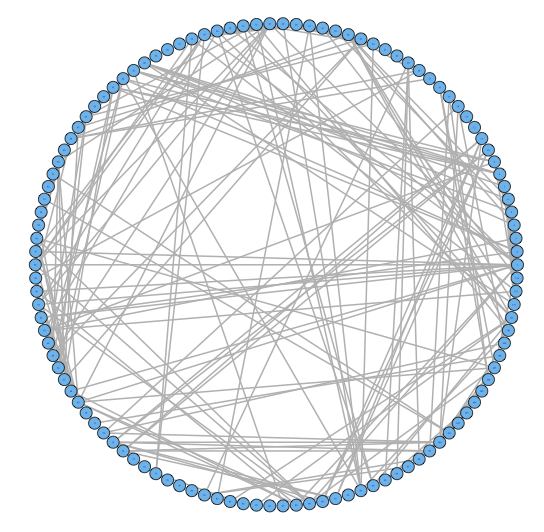

For our two-level problem (1.1.1), we must account for two sources of network variability when conducting population inference: (i) variability between subjects within a group and (ii) variability of the network selection procedure within a single subject. To see this, let us study a real multi-subject fMRI example. In Figure 2, we show estimated functional brain networks for subjects from the UCLA fMRI ABIDE data set INDI (2013). We describe the details of this data set, our pre-processing, and brain parcellation later in the Case Study in Section 5. In the top and middle panels, we estimate brain networks for each subject using graph selection methods for Gaussian graphical models (see Section 3.1 for details) and plot these as circle graphs to easily visualize network differences. It is clear that there are not only differences between autistic subjects and control subjects, but there is also large heterogeneity across subjects within each group. This is well-known in the neuroimaging literature (Milham et al., 2012; Nielsen et al., 2013), and makes finding statistically significant differences between subject groups much more challenging.

Less well studied in neuroimaging, is the second source of variability which arises from estimating networks for each subject instead of directly observing the networks. In the bottom panel of Figure 2, we re-estimate brain networks for a single control subject with bootstrap resampled data. It is clear that there is major intra-subject variability arising from our graph selection procedure. Indeed in neuroimaging, test–re-test studies which conduct brain imaging on the same subject in repeated sessions have shown high variability in the subject’s estimated brain networks (Wang et al., 2011). This also motivates the necessity of using a two-level model like (1.1.1) for population network inference as opposed to the one-level model and test statistics of the standard procedure.